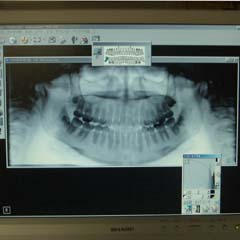

デジタルレントゲンの画像

患者様をお待たせせずに、従来より鮮明な画像を提供します